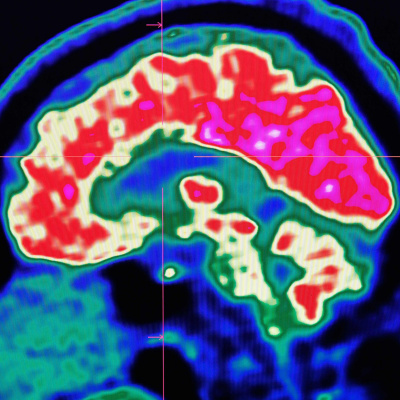

Researchers in the US have for the first time constructed intelligible synthetic speech using the computer processing of human brain activity, in a significant step towards creating technology that can read people’s thoughts. Madhumita Murgia talks to our science editor Clive Cookson about how they did this.Contributors: Katie Martin, capital markets editor, Madhumita Murgia, European technology correspondent and Clive Cookson, science editor. Producer: Fiona Symon See acast.com/privacy for privacy and opt-out information.